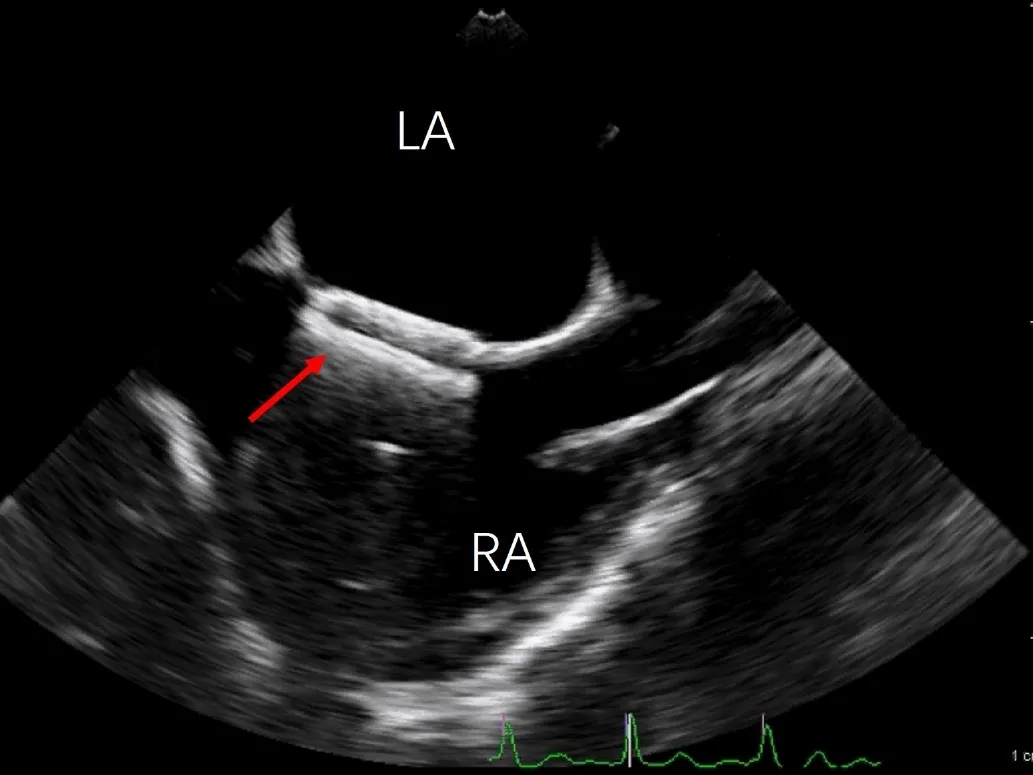

常规经食道超声心动图(TEE)评估发现,左心耳血流速度明显减慢,流速约 24 cm/s,提示存在血栓形成高风险因素,但左心耳内未见自发显影。此外,TEE发现巨大房间隔膨胀瘤(ASA,大小约28×10mm),同时合并卵圆孔未闭(PFO),且ASA腔内可见明显自发性显影(SEC),其内血流速率明显减慢(20.8cm/s)。

巨大房间隔膨胀瘤及自发显影